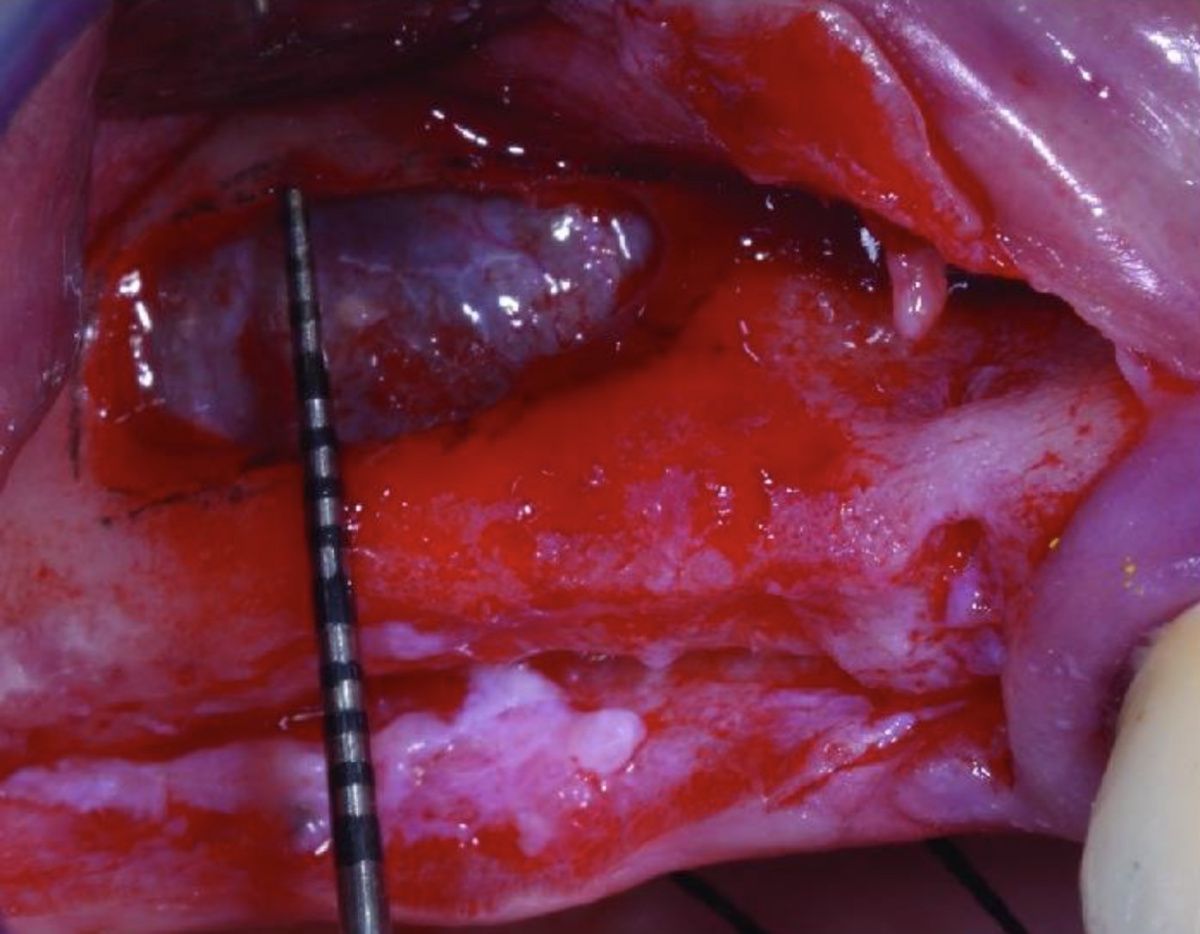

Другим методом предотвращения повреждения ААА является бережное удаление костной ткани с помощью костных скребков [20,21].

Использование костных скребков при антротомии является довольно простой и безопасной процедурой. Также костный скребок позволяет собирать аутогенный костный материал в виде частиц, который может быть использован при проведении аугментации.